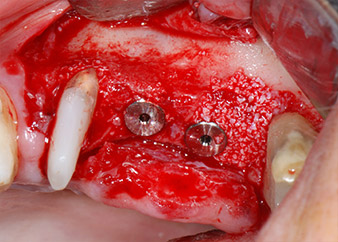

тотална загуба на кост и захват

Фиг. 2 и 3: След повдигане на ламбото, един месец след ендодонтския преглед и прилагане на цялостна периодонтална терапия в цялата уста, букалният корен на зъб 24 разкри тотална загуба на кост и захват.

След един месец, в деня на операцията, болката и възпалението в зъб 24 е минимално, но подвижността в Miller class 2 е на лице. След отваряне на ламбата и почистването на периапикалната и перирадикуларната тъкани, обхватът на костния дефект стана очевиден (Фиг. 2 и 3).

В букалния корен, цялата вестибуларна и дистална кост липсва. Захващането е значително ограничено до палатиналния корен, подчертавайки предварително лошата прогноза. Зъб 27 също откри намалено хоризонтално захващане и минимално апикално разреждане (Фиг. 1) без клинични симптоми.